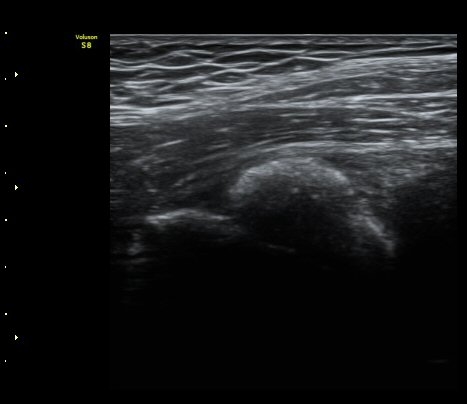

ÃÊÀ½ÆÄ °Ë»ç

¾ûµ¢ÀÌ °üÀý Á¾´Ü¸é°Ë»ç¿¡¼­ ƯÀÌ ¼Ò°ßÀ» º¸ÀÌÁö ¾ÊÀ½(»çÁø 1).